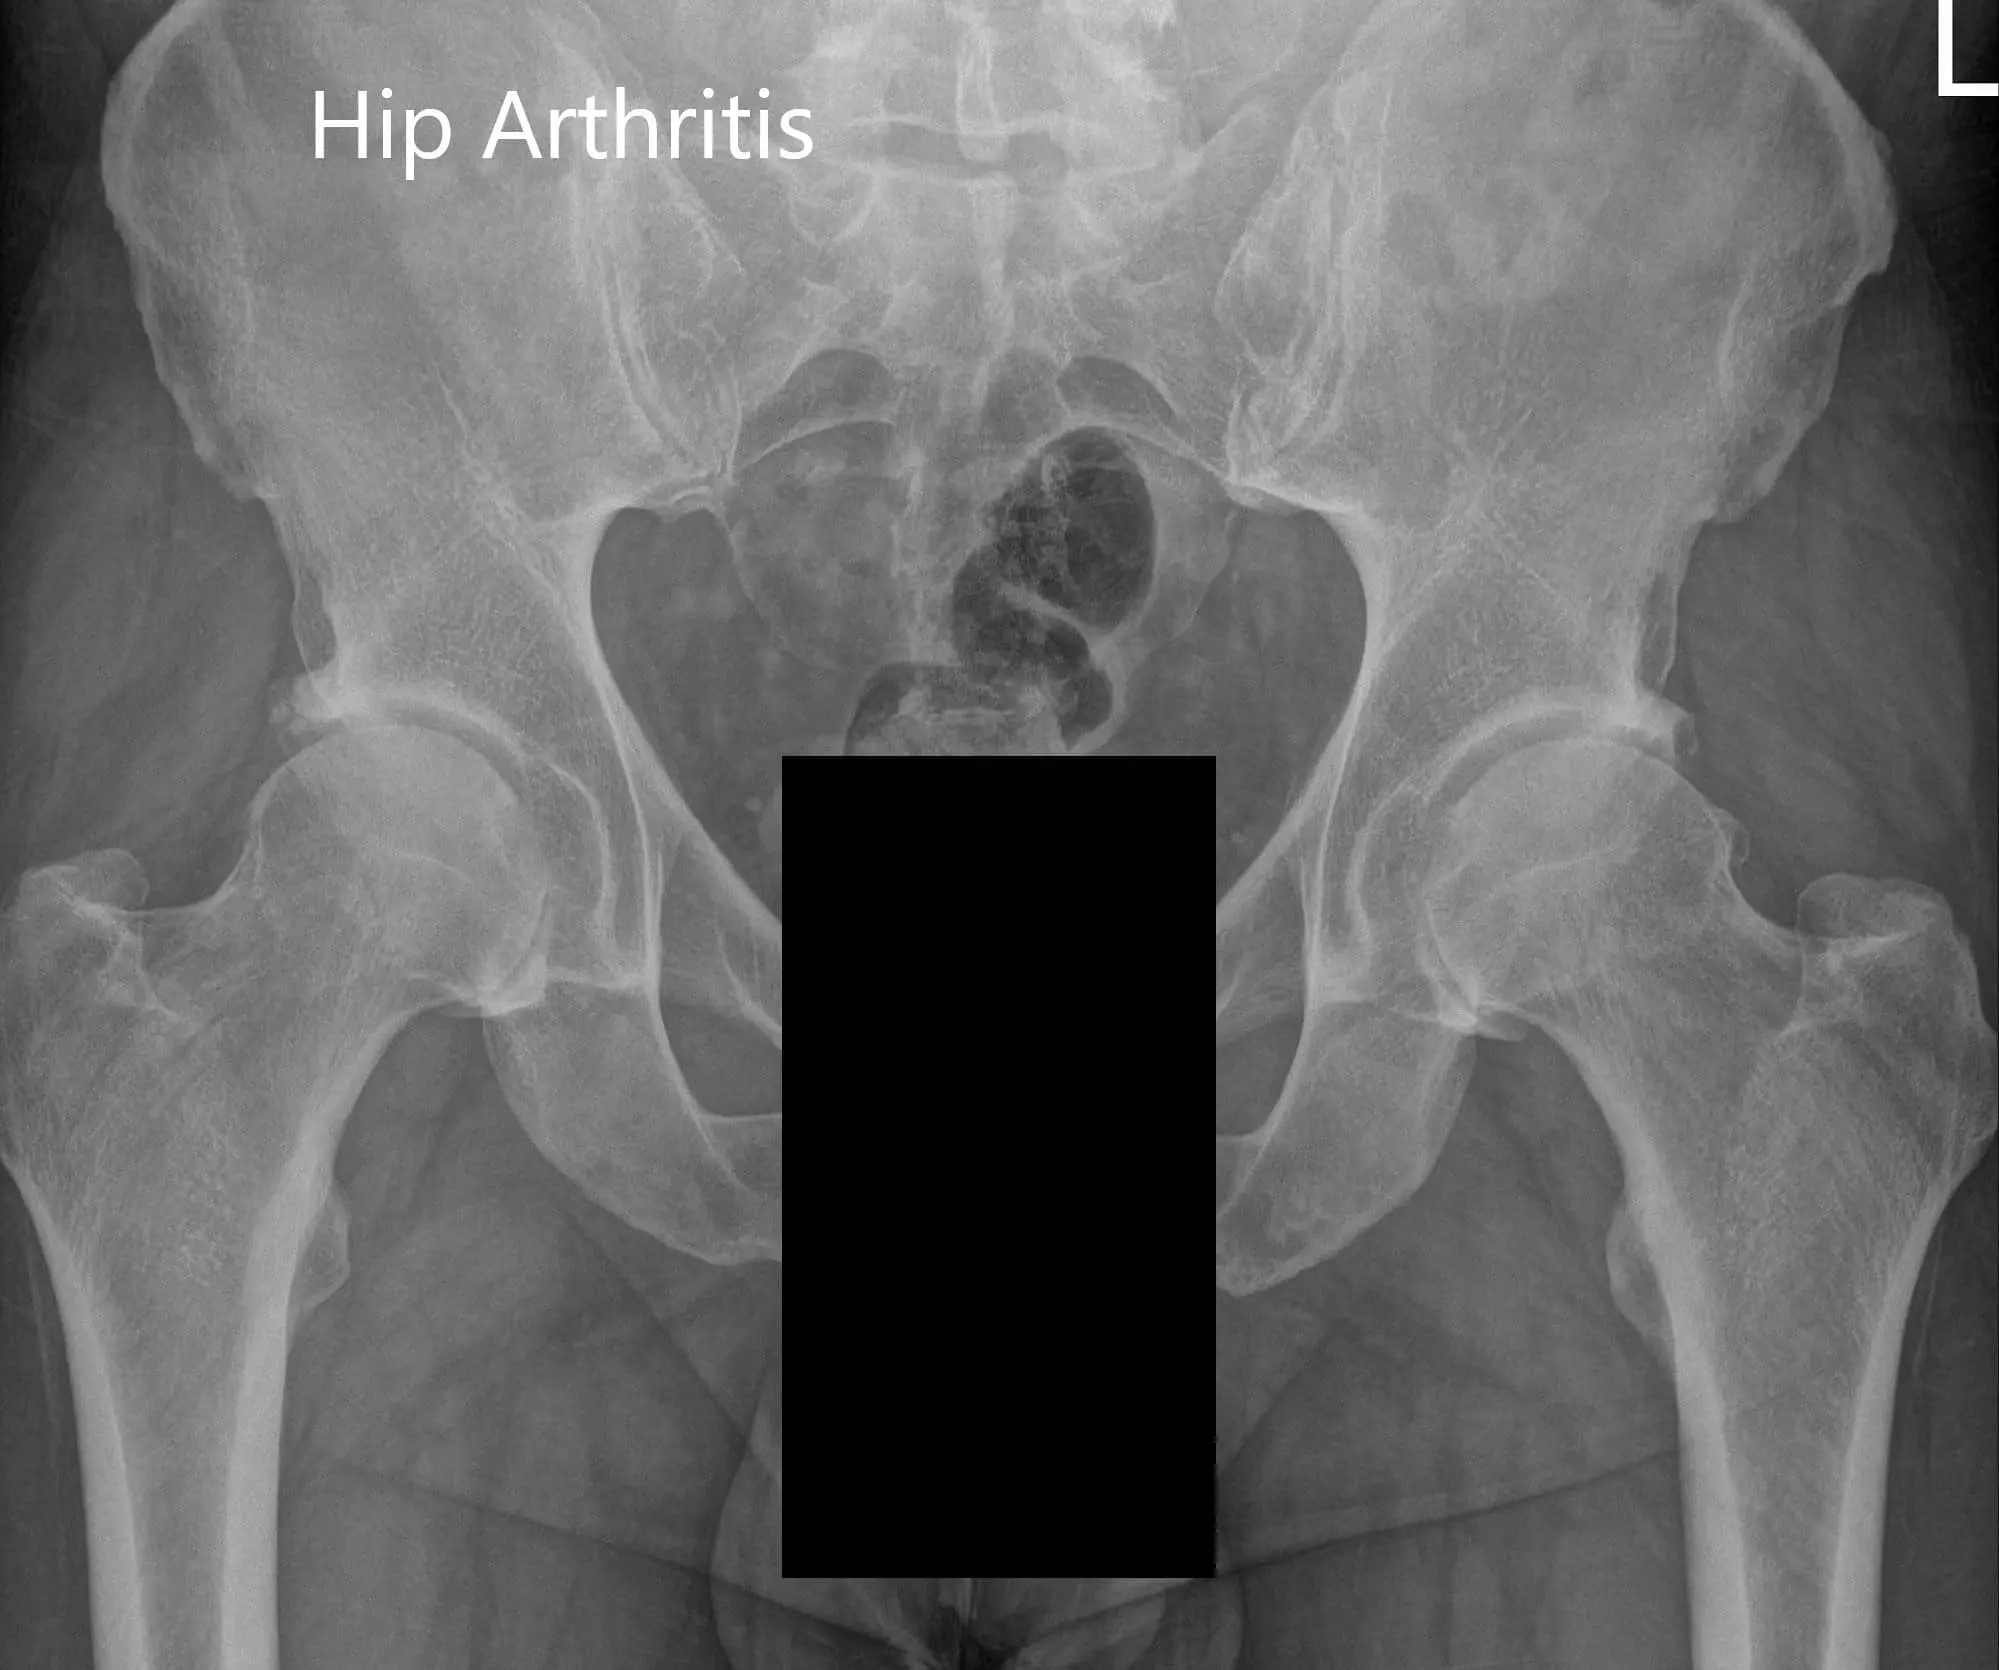

Her imaging studies revealed arthritis changes in both her hips. Considering her lifestyle limiting hip pain, she was advised to undergo bilateral hip total replacement. Risks, benefits, and alternatives were discussed with her as well with her husband at length. She agreed to go ahead with left hip replacement.

Preoperative X-ray of the pelvis AP view and the lateral view of the left hip.